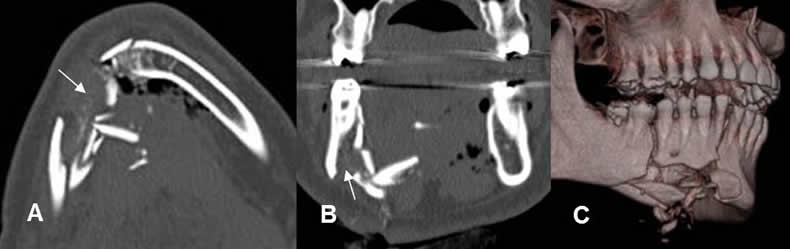

Fig 75. Trauma.

A: TAC axial, B: TAC reconstrucción coronal y C: TAC reconstrucción 3 D. Fractura conminuta, que afecta el borde inferior de la sínfisis mandibular. Por su localización, debe sospecharse lesión del canal dentario.